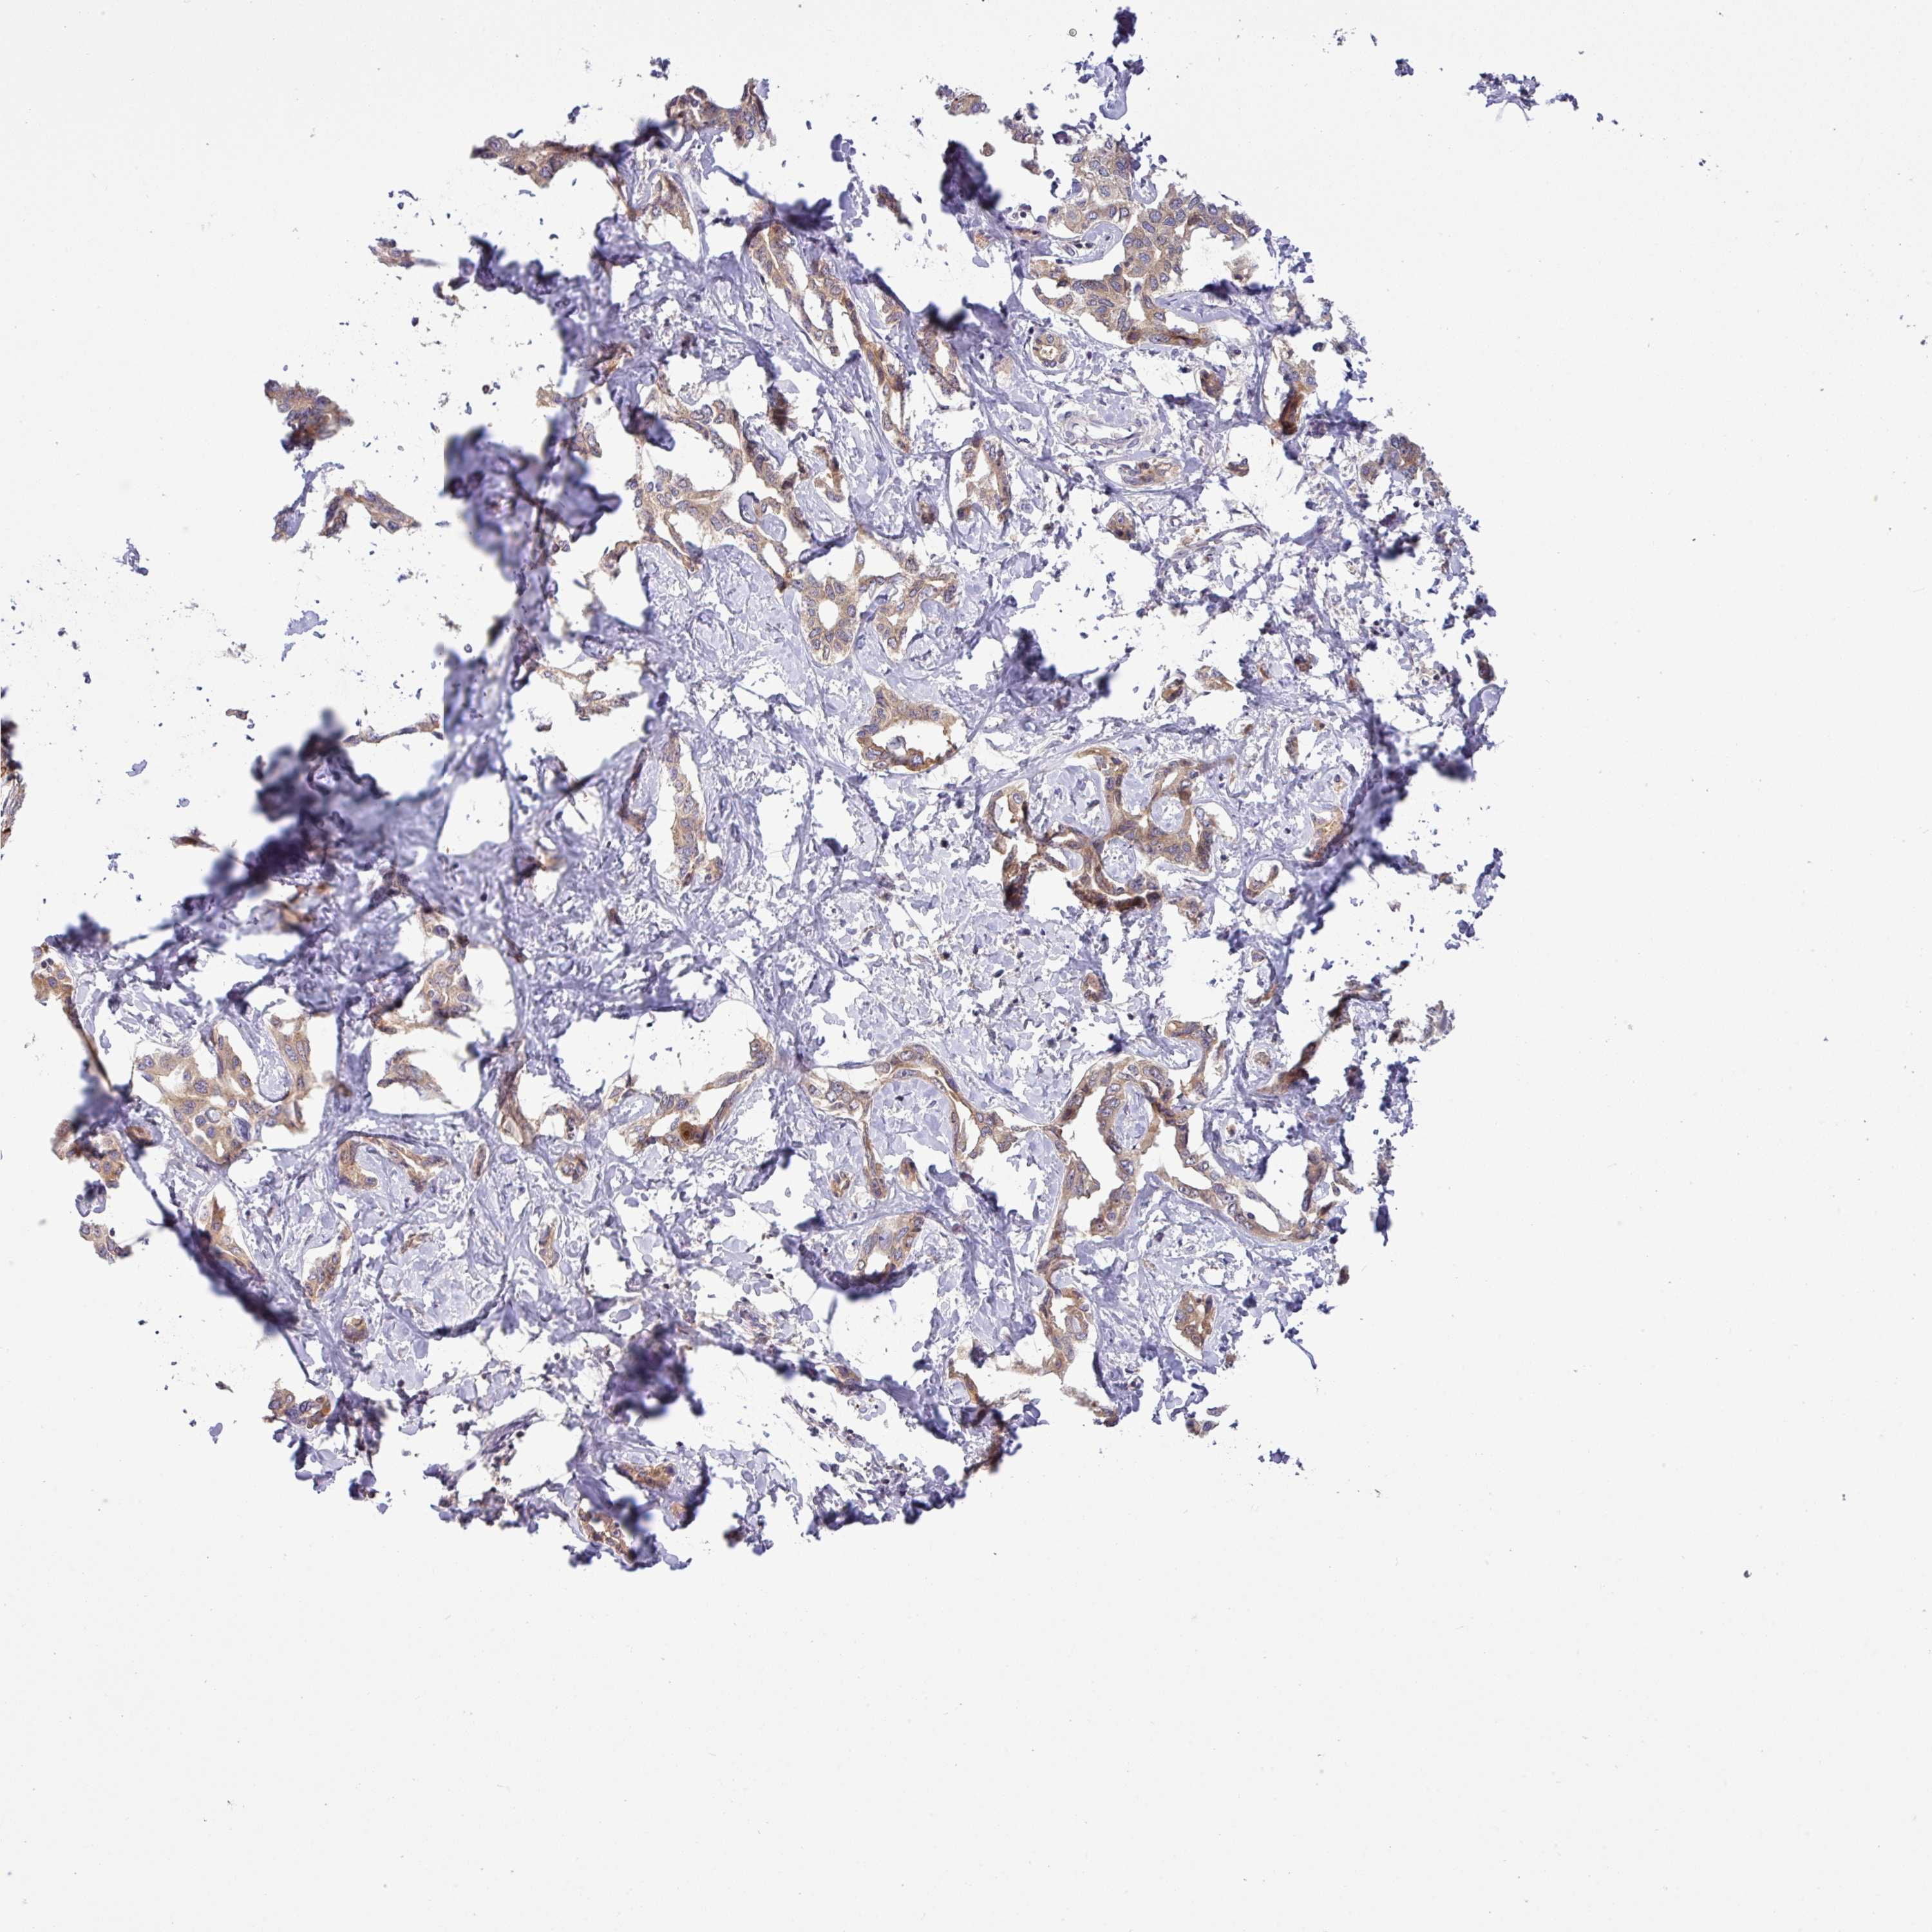

LIVER CANCER - Protein expressioni

A mouse-over function shows sample information and annotation data. Click on an image to view it in a full screen mode. Samples can be filtered based on level of antibody staining by selecting one or several of the following categories: high, medium, low and not detected. The assay and annotation is described here.

Antibody stainingi

Antibody staining in the annotated cell types in the current human tissue is reported as not detected, low, medium, or high, based on conventional immunohistochemistry profiling in selected tissues. This score is based on the combination of the staining intensity and fraction of stained cells.

Each image is clickable and will lead to virtual microscopy that enables deeper exploration of all samples and also displays staining intensity scores, fraction scores and subcellular localization as well as patient and tissue information for each sample.

Antibody HPA044461

Staining

High

Medium

Low

Not detected

Intensity

Strong

Moderate

Weak

Negative

Quantity

>75%

75%-25%

<25%

None

Location

Nuclear

Cytoplasmic/membranous

Cytoplasmic/membranous,nuclear

Cholangiocarcinoma

Carcinoma, Hepatocellular, NOS